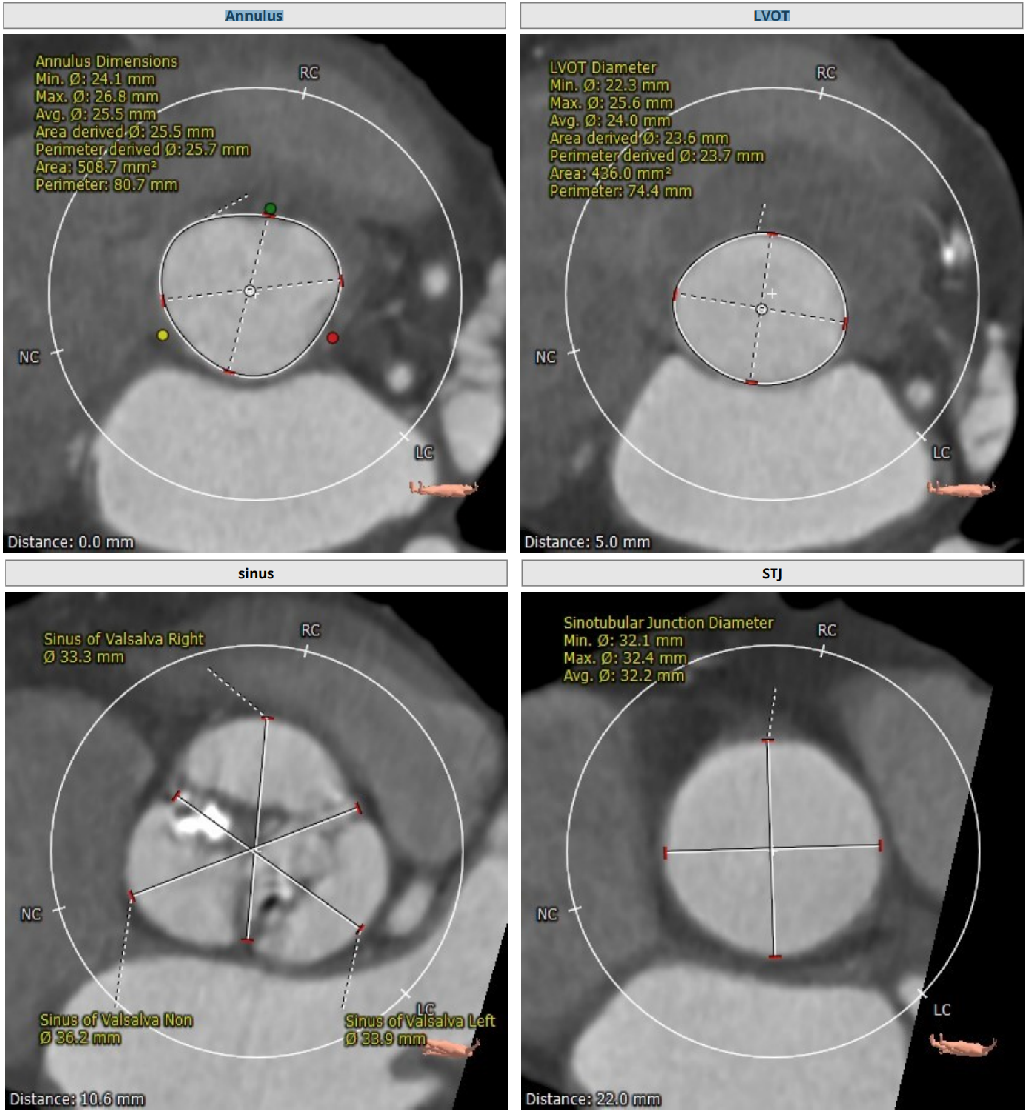

Annulus25.7mm

LVOT:24.0mm

STJ:32.2mm

升主动脉:35.9mm

LM:13.2mm

RM:16.1mm

CT分析

Anulus 25.7、LVOT 23.7;STJ高度可,窦部空间足够;初步预估29/32瓣膜。

升主未见增宽,角度尚可,轻度钙化。

左右冠高度不低,球扩体位:LAO 26、CRA 18;释放体位:LAO 9、CRA 4;心室腔略小。